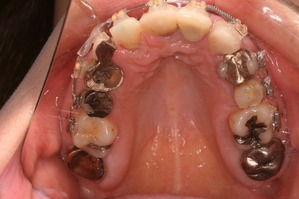

おおよそ1年間の治療期間で歯の根っこと矯正治療が終了しました。

この後、下の前歯1本が暗いのでホワイトニングをし、上下の歯のかぶせ物をやりなおす治療へと移行していきます。

上からみてもかなり左右対称な関係になります。